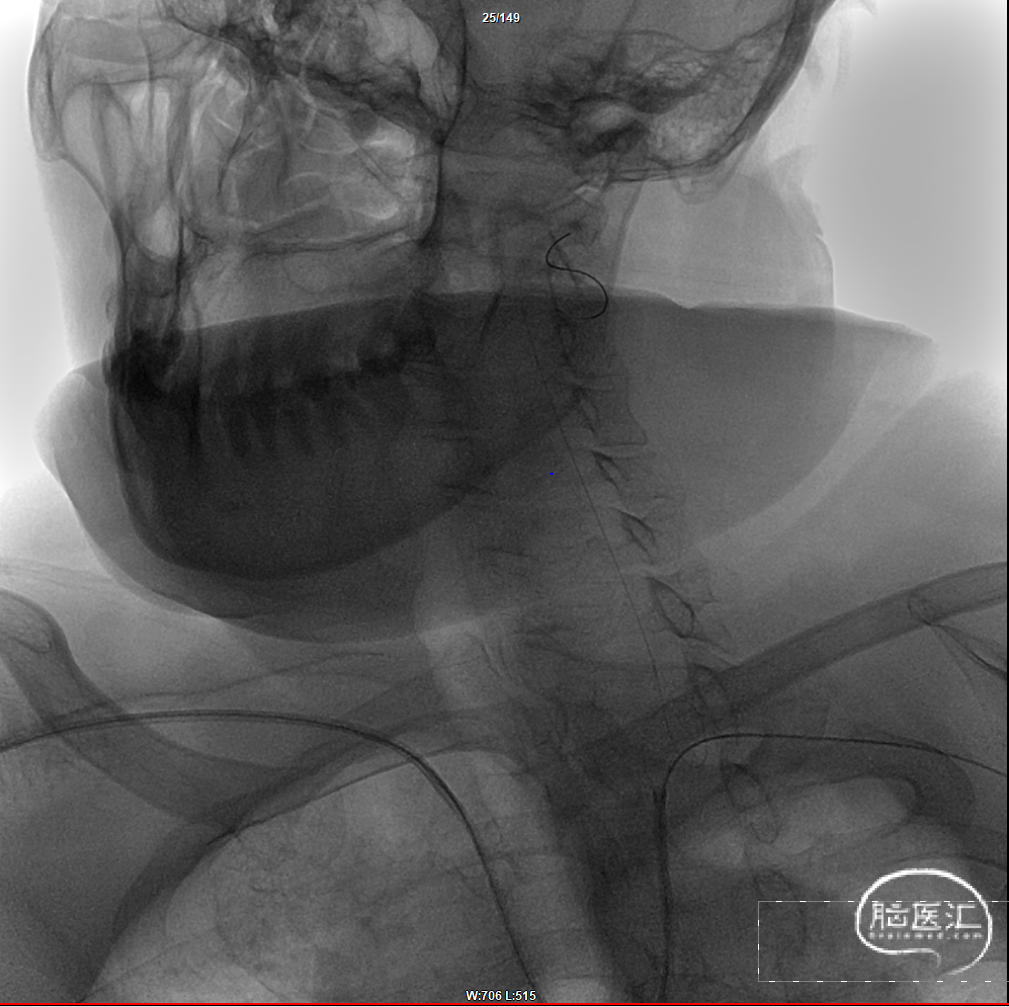

术后造影:

正位

侧位